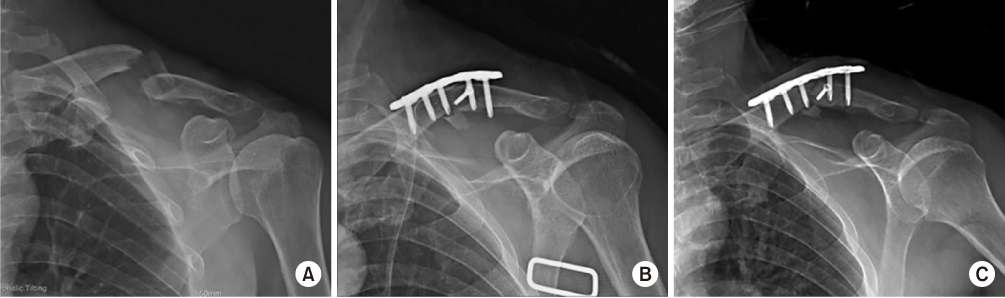

Fig. 4

(A) Immediate postoperative radiograph after the second surgery. Callus bridging is seen on the 3-month follow-up radiograph (B) and consolidation processing on the 6-month follow-up radiograph (C).

On postoperative day 1, the patient presented with improved strength of thumb flexion and finger flexion to a grade 3/5 with decreased numbness of the left hand. On postoperative day 3, wrist extension improved to a grade 2/5 and left hand numbness was nearly resolved. Electromyography at 12 days postoperatively demonstrated diffuse brachial plexopathy, especially affecting the upper trunk. The patient underwent physical and exercise therapy until discharge. At the time of discharge, on postoperative day 30, thumb extension and finger extension and abduction were graded as 3/5, and all other left hand strengths were graded as 4/5. A Velpeau sling was not applied after discharge. On radiographs 3 and 6 months postoperatively, callus bridging and consolidation were visible (Fig. 4). On examination, there was no excess motion or tenderness at the fracture site, shoulder abduction and flexion were graded as 3/5 and 4/5, respectively, and all hand and elbow functions were fully recovered.